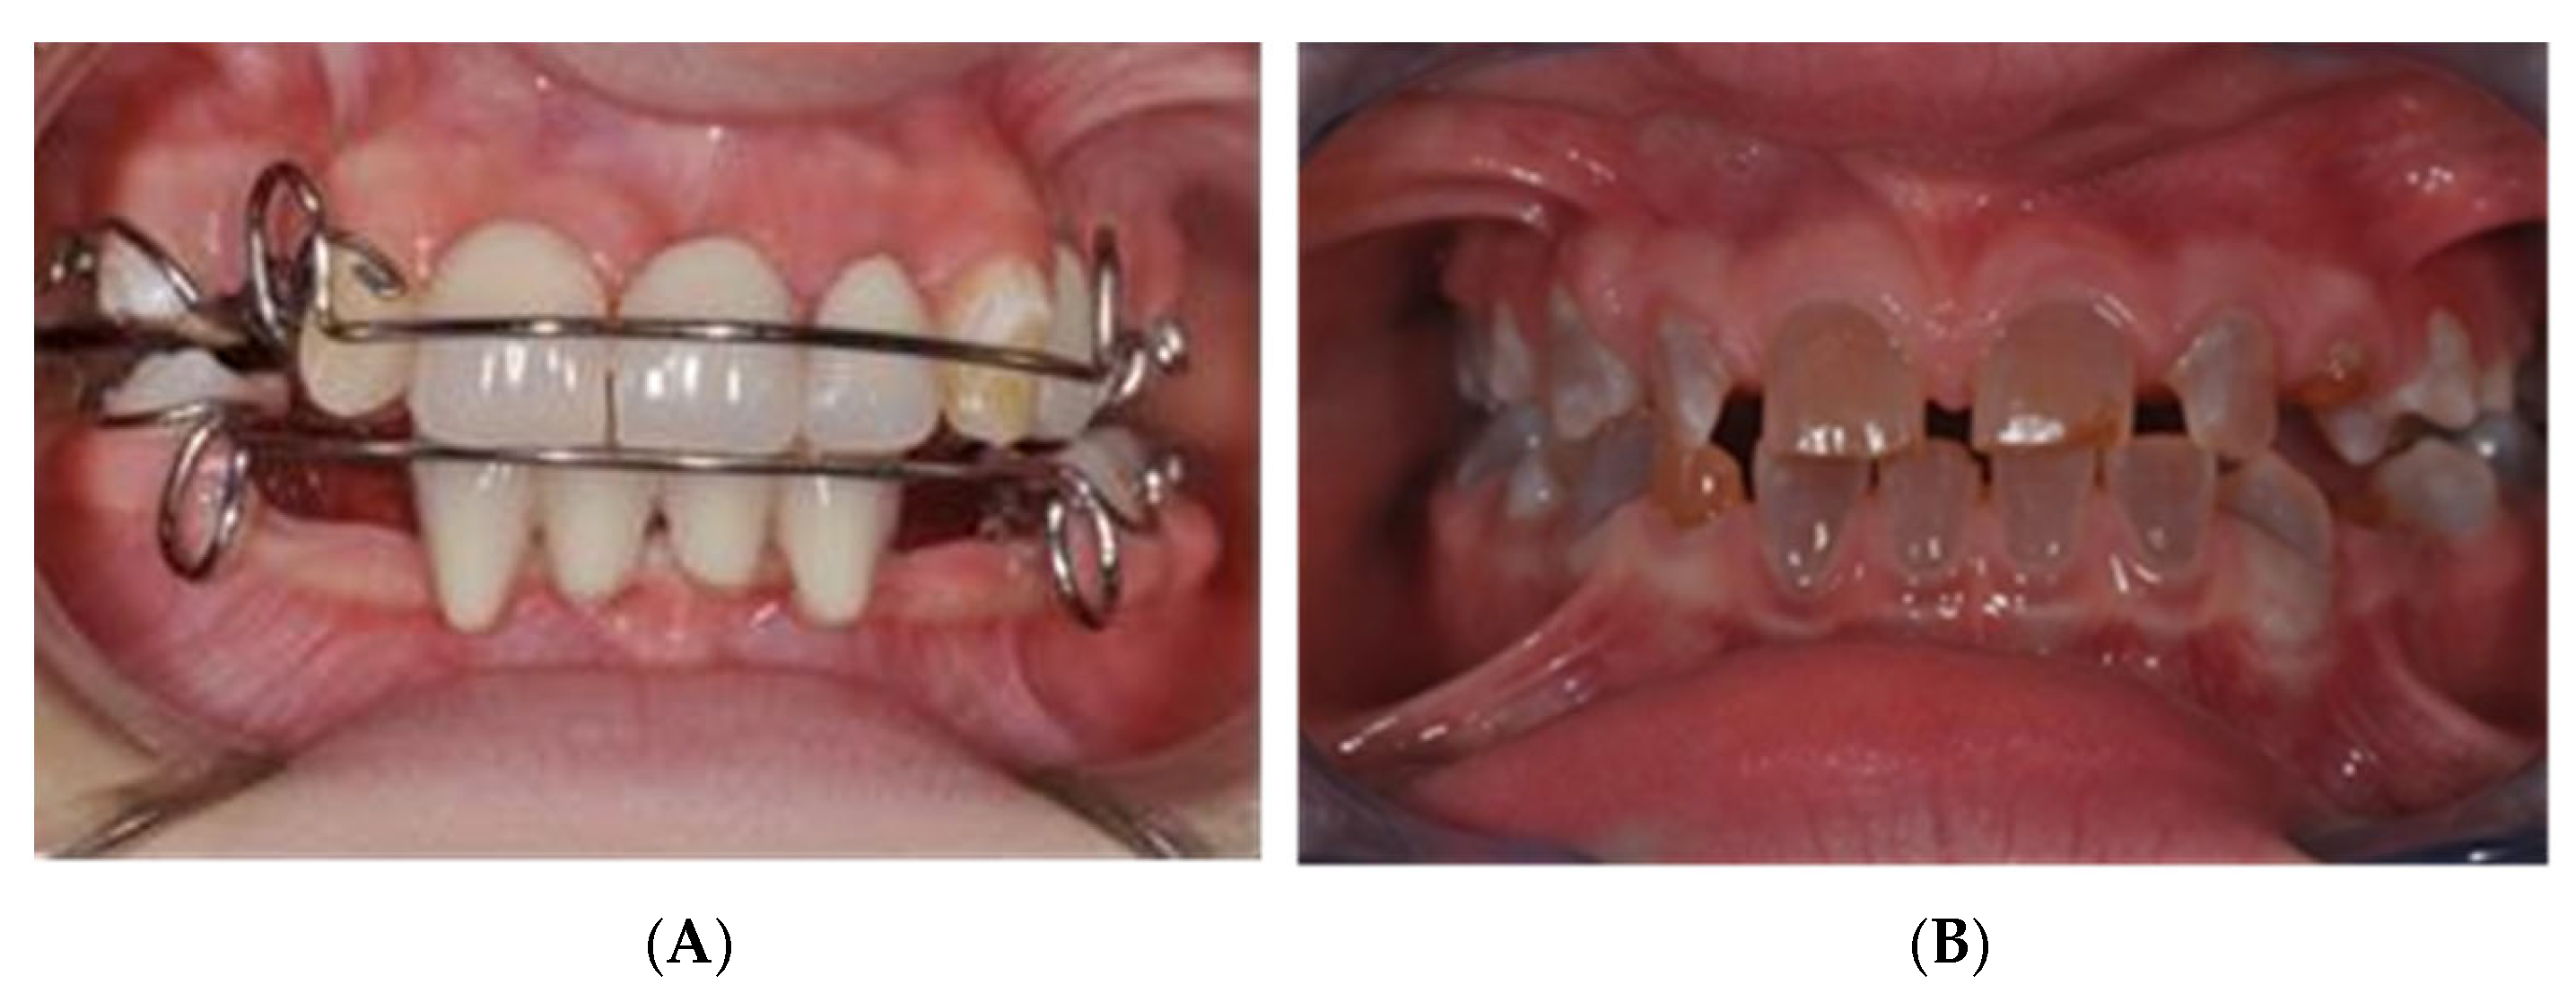

2.2. MSE Treatment in Patients with Osteogenesis Imperfecta and Dentinogenesis Imperfecta